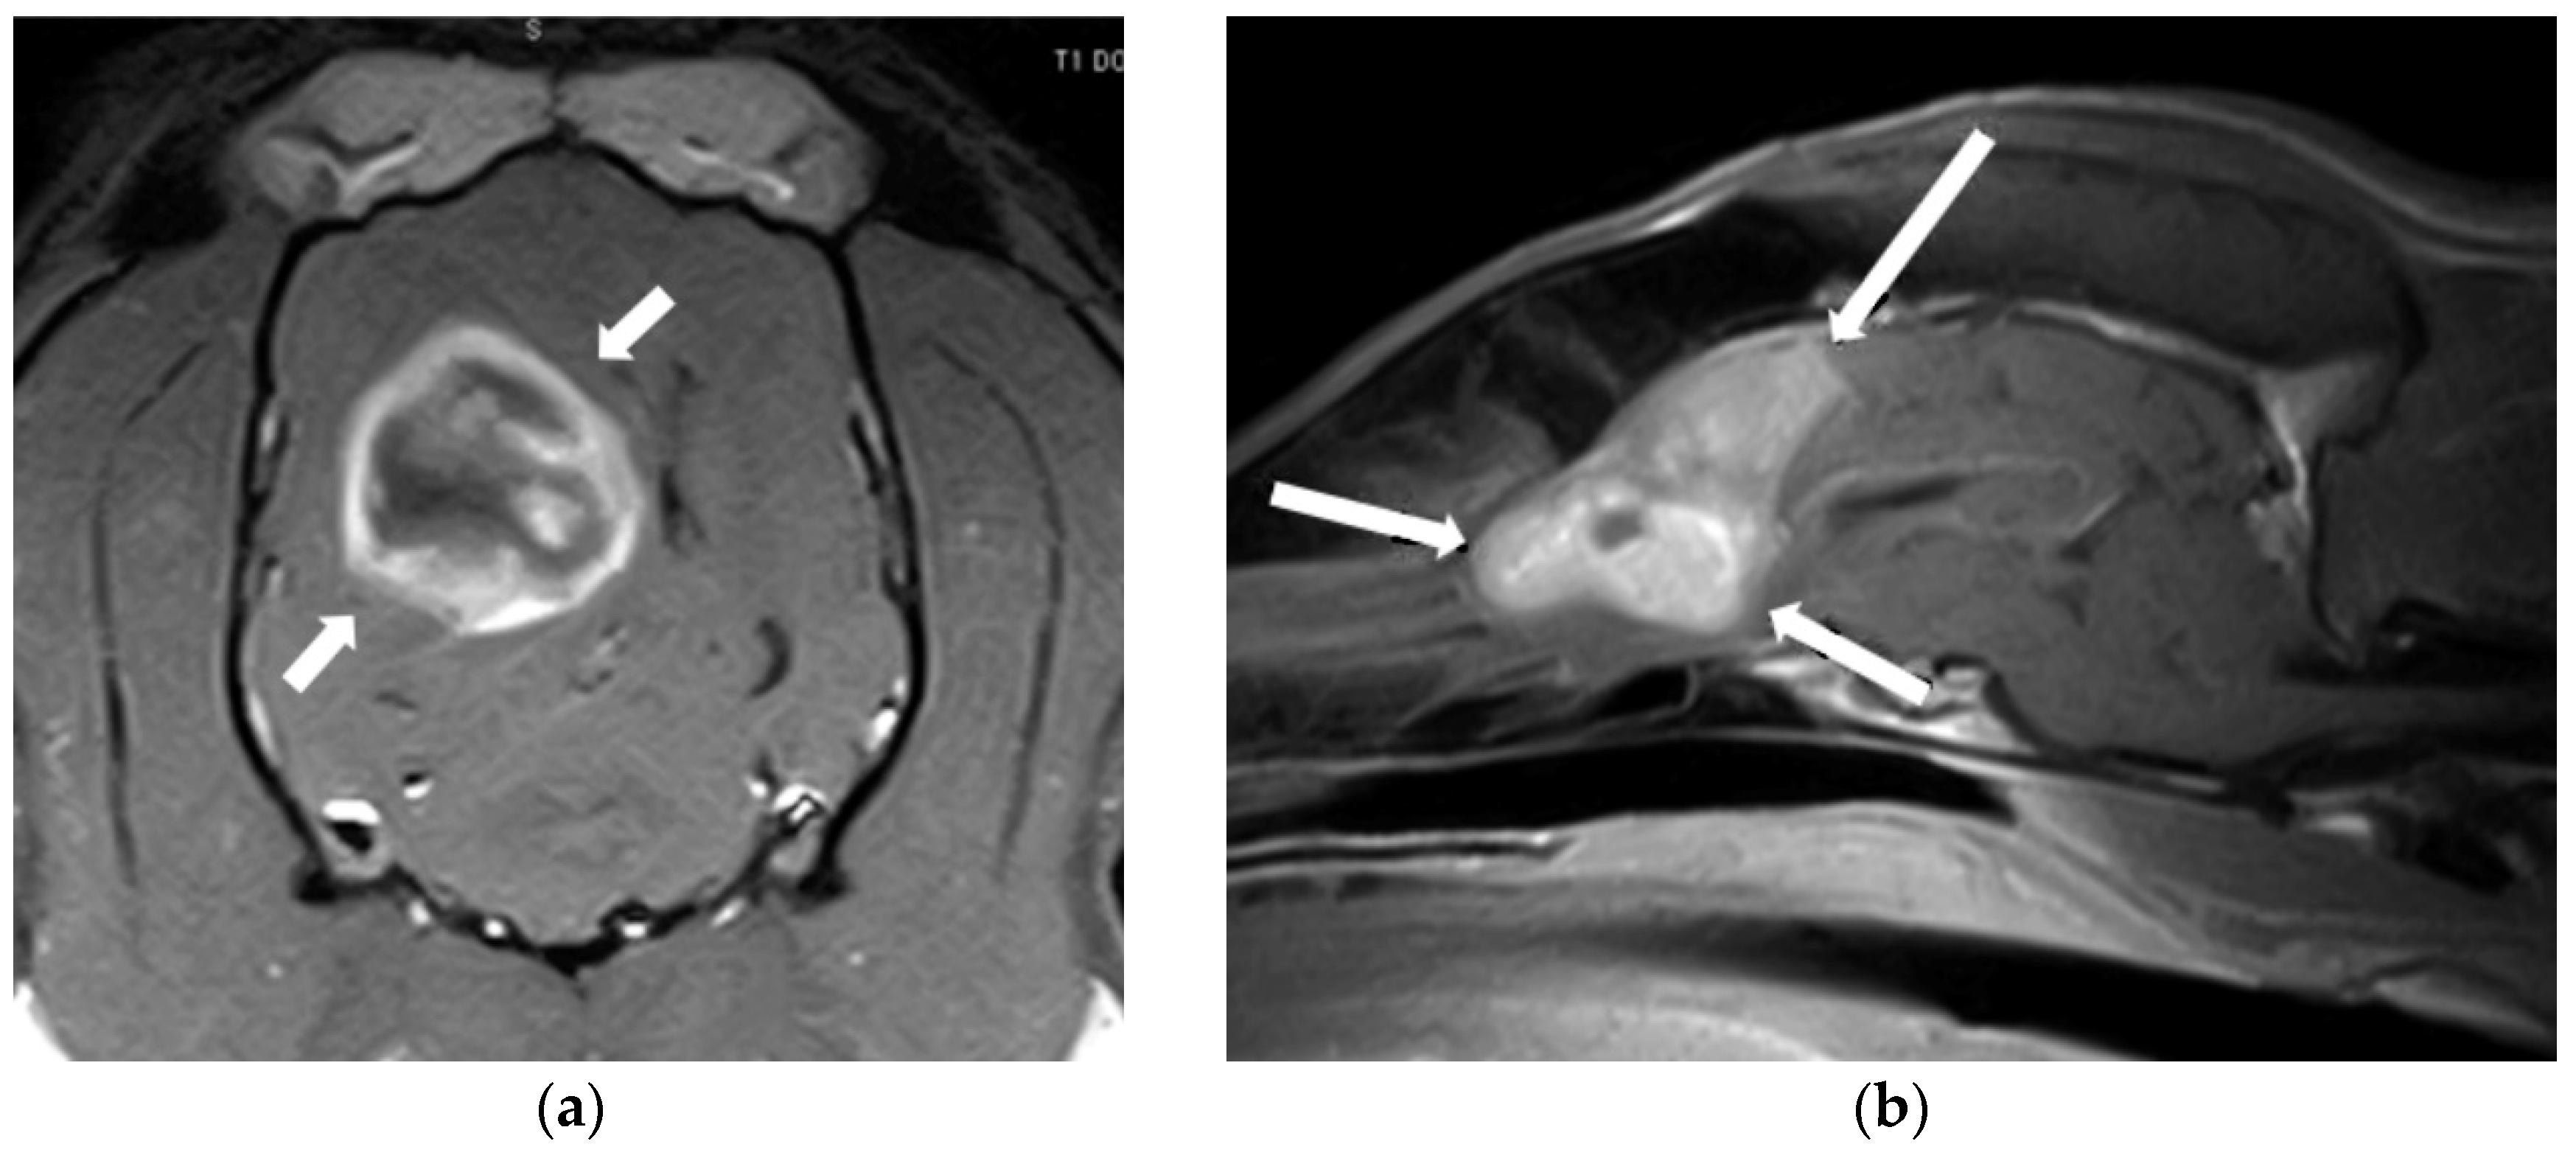

3.1. Intervertebral Disc Disease